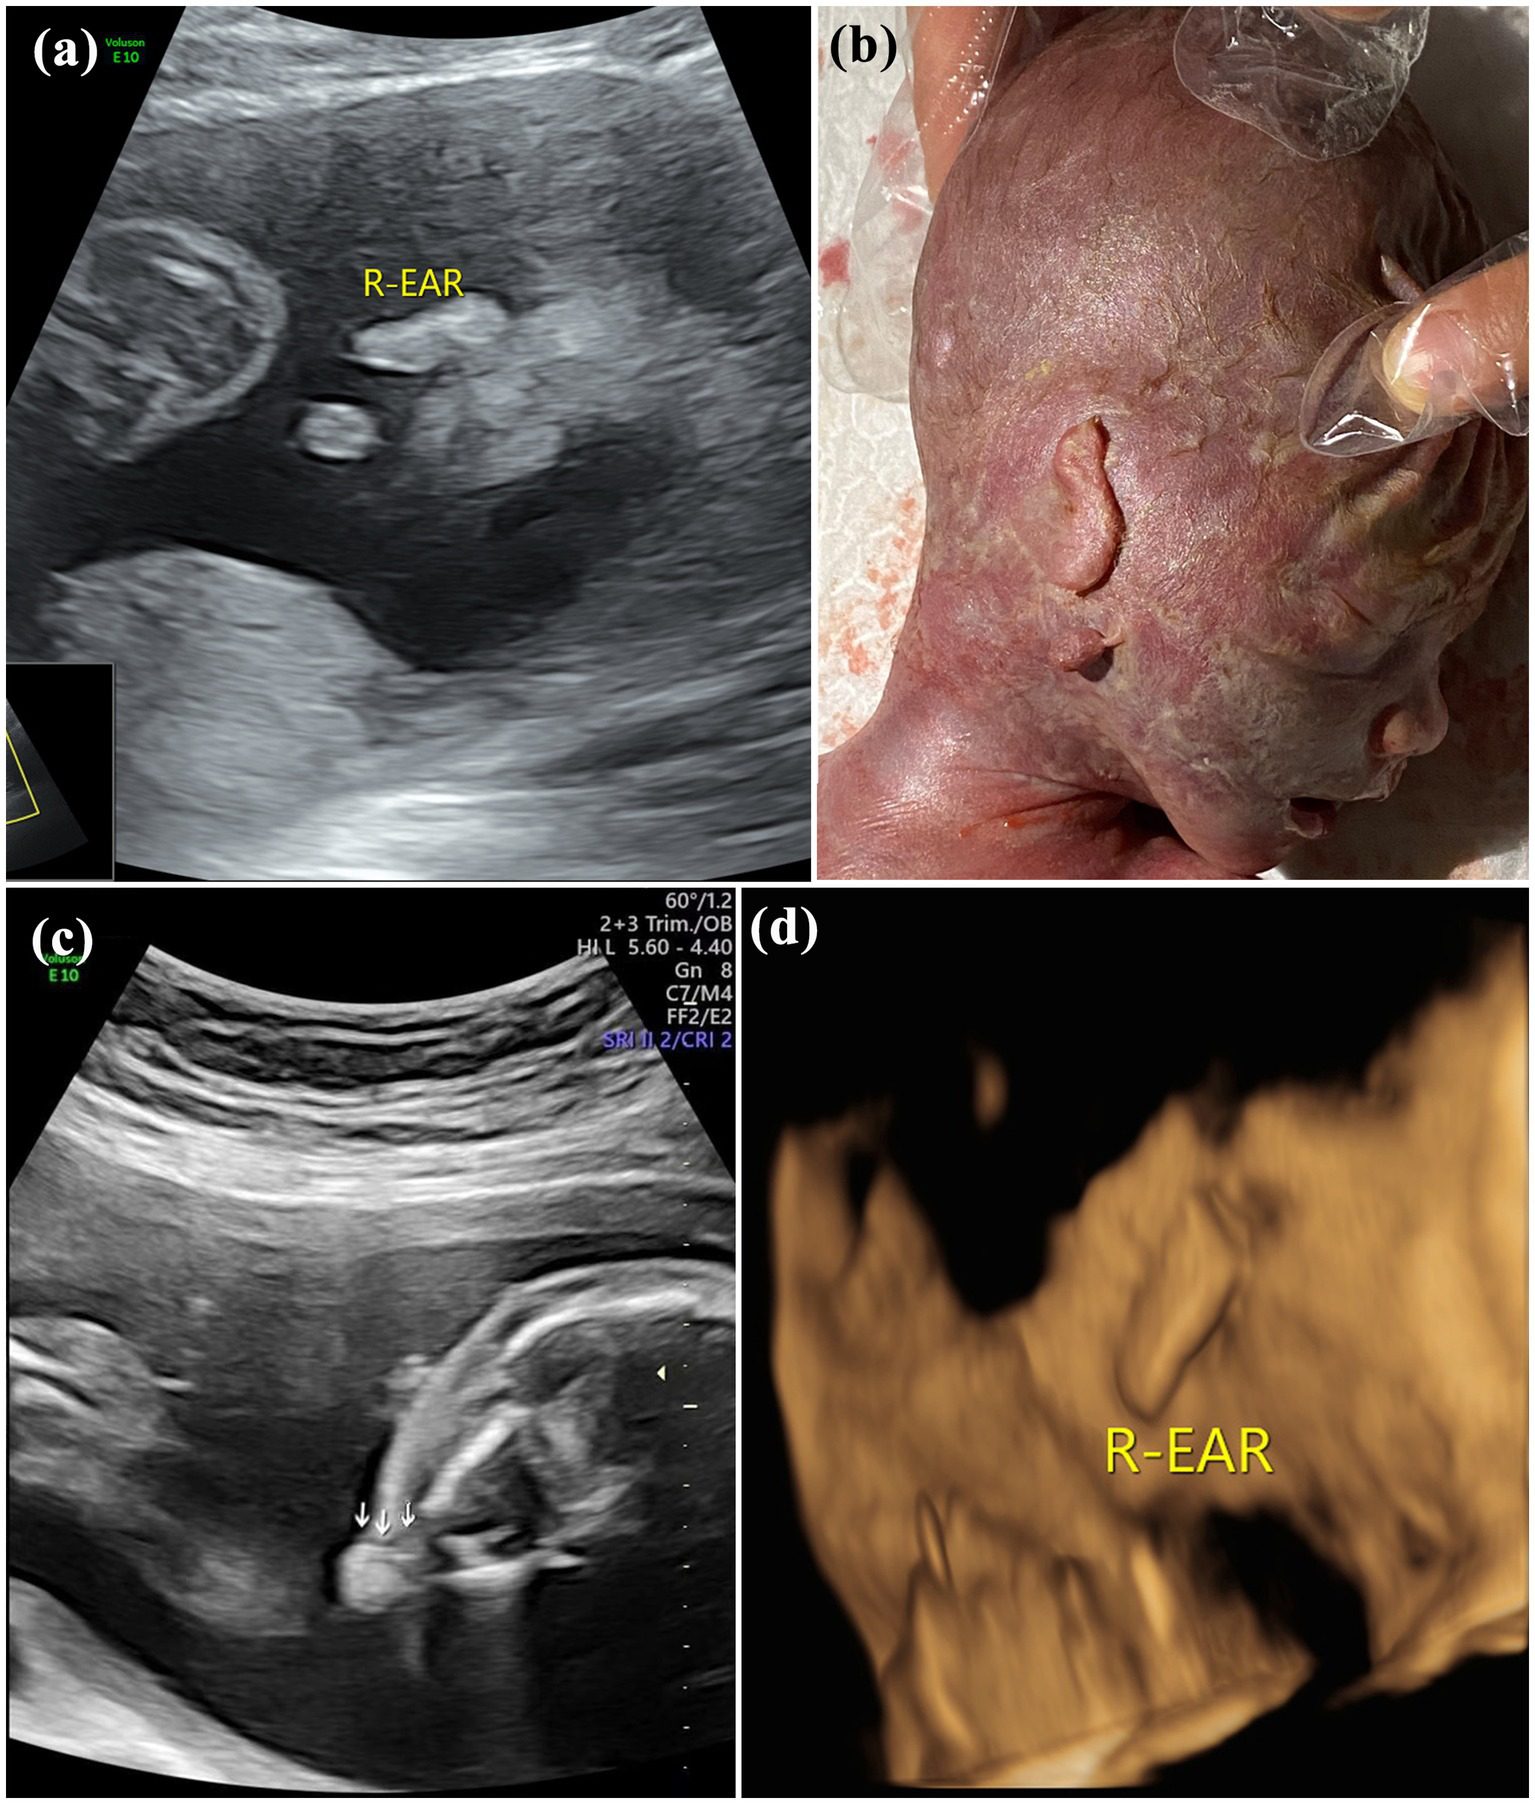

Pregnant women were placed in the supine position under obstetric conditions. The structural development of the fetuses was systematically screened by ultrasound, and biological diameters were measured. In our study site, fetal auricles were generally observed on the parasagittal plane of the temporal bone, and the probe was deflected left and right on the sagittal plane of the fetal brain or face to display the bilateral auricles. Multiplane scans (including the coronal plane and cervical posterior transverse oblique plane) and 3D imaging were further performed in cases with suspected auricle abnormality (Figure 1).

Figure 1

Images of normal fetal ear: (A) 2D sonography and (B) 3D sonography.